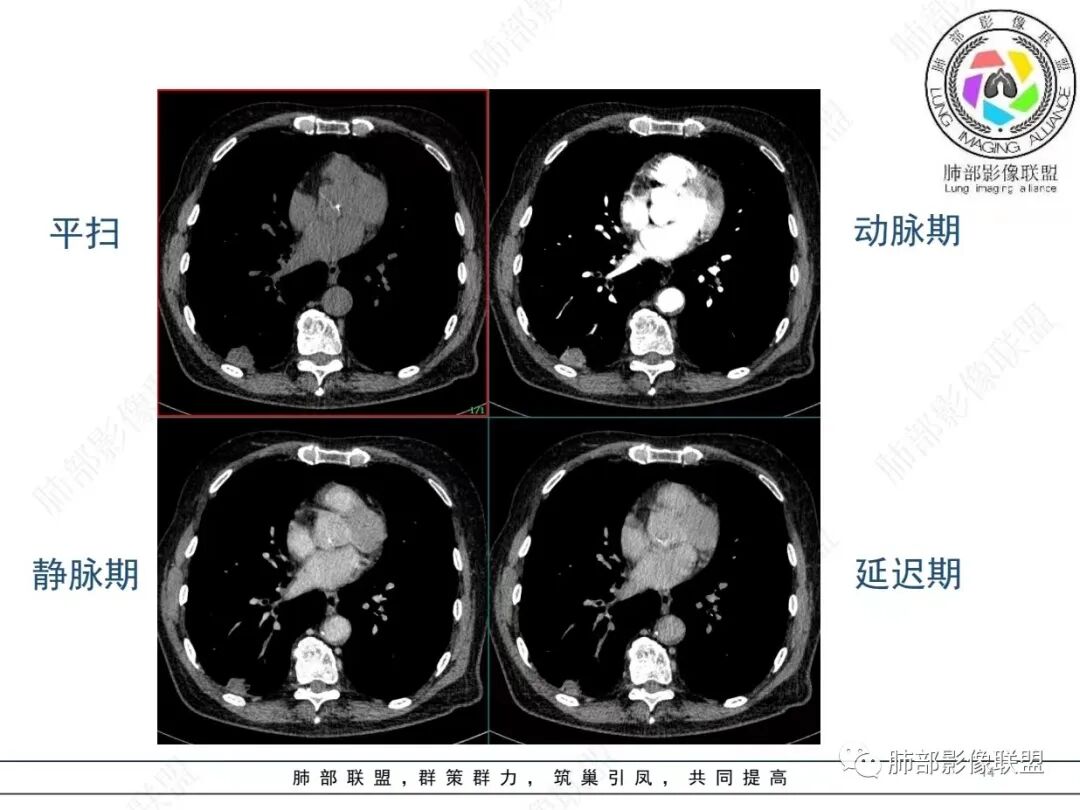

老年男性,发作性气喘,实验室检查白细胞增高。肺部影像表现:右肺胸膜下占位性病变,肺气肿背景,内部可见空腔/空泡影,周围可见小结节,增强动脉期明显强化,静脉期及延迟期强化减低,右侧肺门可见肿大淋巴结,有吸烟史,近年减少,首先考虑恶性肿瘤,肺小细胞癌/鳞癌,隐球菌作为鉴别诊断,病例穿刺活检。

老年男性,气短,胸痛半年,考虑慢性病史,无发热,常见的肺部感染可以排除,右肺下叶基地段靠近胸膜实变影,边缘清楚,不均匀强化,可见空泡征,点状血管影,周围小叶中央型结节,有网格影,支气管扩张,磨玻璃影,肺间质改变,右侧肺门淋巴结肿大,综合考虑恶性肿瘤并肺内转移

老年男性,肺气肿背景,右肺下叶,右肺下叶胸膜处实性结节,形似山丘,有分叶,病灶内可见扩张细支气管/空泡,边缘可见弯曲血管,增强后不均匀强化,可见血管影,病灶胸膜侧呈小波浪??状,局部突入胸膜面,右肺门肿大淋巴结。考虑恶性结节,小细胞肺癌,腺癌,鉴别炎性肉芽肿。建议ct下穿刺活检。

老年男性,肺气肿病史,支气管束增粗,管壁增厚,右肺下叶后基底段胸膜下肿块,土豆征,边界清,有膨隆,小支气管边缘阻断,见集血管束征,肿块强化明显(快进快出特点),并偏心空洞,胸膜下栽赃,周围肺结构破坏(蜂窝状影表现),右肺门淋巴结转移肿大,血管内皮生长因子偏高,肿块与小支气管,血管束关系密切,强化特点,定恶性肺肿瘤,小细胞Ca。

老年男性,肺气肿,右肺下叶胸膜下结节,边缘毛躁,周围多发间质增厚,临近胸膜下脂肪间隙模糊,增强后动脉期不均匀强化,延迟期强化较低,右肺门肿大淋巴结,考虑恶性,鳞癌,小细胞肺癌,鉴别炎性肉芽肿性结节

右下叶胸膜下结节,宽基底与胸膜相连,结节与胸膜相交呈钝角〈山丘征〉,内可见充气扩张的支气管,中度强化,结节边缘无毛刺,内见走行自然的血管影,提示破坏力及收缩力差,右肺门可见肿大淋巴结,老年烟民,考虑恶性占位,支持小细胞癌

右肺下叶胸膜下结节,呈山丘状,生长在慢支肺气肿间质纤维化的基础上,边缘相对光滑清晰,右肺门淋巴结肿大,强化呈速升速降,老年男性,吸烟史,考虑小细胞肺癌,鉴别隐球

恶性明确(右肺门淋巴结明显肿大,中心坏死,坏死边界不清楚,胸膜下馒头样肿块,血管集束,支气管阻塞,动脉期明显强化,内部明确的供血血管提示肿瘤细胞密集,局部坏死边界不清,强化快进快出,邻近胸膜强化呈胸膜尾征,提示胸膜受侵),病理符合周围性低分化鳞癌(老年男性,长期吸烟史,肿块强化明显,快进快出,坏死边界不清楚,阻塞性炎症及阻塞性肺气肿,肺门淋巴结肿大,坏死,邻近支气管壁增厚支持粘膜下侵润生长),白细胞总数高,动脉期强化那么明显,腺癌合并感染倒是要高度警惕。

老年男性,吸烟史+肺气肿背景,右下肺胸膜下肿块(坏死+内部血管影+快进快出),右侧肺门淋巴结肿大,考虑:恶性、鳞?高级别腺待排(总体感觉偏软)。

男,80,发作性气喘半年,加重1天。长年大量吸烟史。肺部CT:肺气肿背景,右肺胸膜下实性占位,处于外周大疱带与气肿带交界,山丘征,边缘膨隆,边界较清,血管集束,周围可见小结节。增强不均匀强化,内可见迂曲模糊血管影,右肺门、隆突下可见肿大淋巴结。首先考虑恶性肿瘤,小?鳞?鉴别PC、TB等。

以后要注意一个重点细节了,对于影像主体类似鳞癌改变的老烟鬼,同时出现引流支气管壁增厚的,主体结节周围有结节堆积感(实际为气道播散)而且强化较明显的,要把大神泌作为鉴别,已经至少有3例这种了。